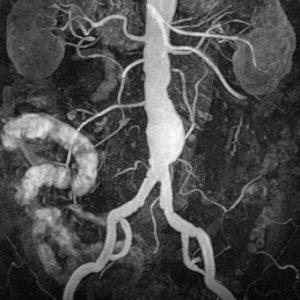

Abdominal aortic aneurysm (enlarged area in the lower part of the aorta) seen by MRI